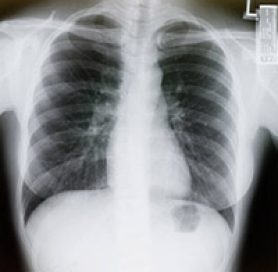

A draft recommendation by a federal task force in favor of using low-dose CT scans to screen past and current heavy smokers for lung cancer provides insight about the time lag.

While low-dose CT scanning identified lung cancer at its earliest, most treatable stage, 96% of the potential tumors identified turned out to be false positives. Additional imaging usually cleared these up, but in some cases, invasive biopsies were necessary to sort cancer from harmless growth.

Screening that leads to over diagnosis and overtreatment is a concern. And the radiation from multiple CT scans also poses risks, even though the low-dose technique uses only a fraction of the radiation of a normal CT scan. The task force took time to weigh the evidence and found that the benefit in saved lives is greater than the risks posed by screening in its eagerly awaited ruling.